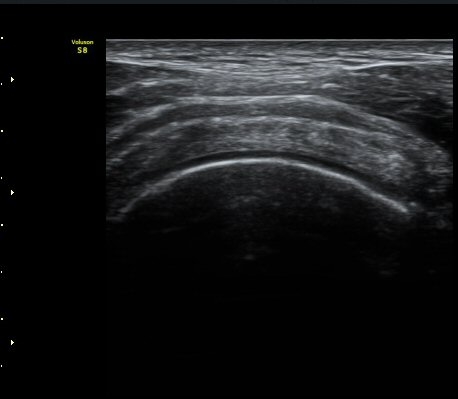

±Ø»ó°Ç Á¾´Ü¸é°Ë»ç¿¡¼­ ±Ø»ó°Ç ÆÄ¿­Àº º¸ÀÌÁö ¾ÊÀ¸³ª »ó¿Ï°ñ ´ë°áÀý°ú °ñµÎ ÀÌÇàºÎÀ§¿¡¼­

ÇÇÁú°ñ ¿¬°á ¼Ò½Ç°ú ¹Ì¼¼ÇÑ °ñÆíÀÌ °üÂûµÊ(»çÁø 3, 4, 5).